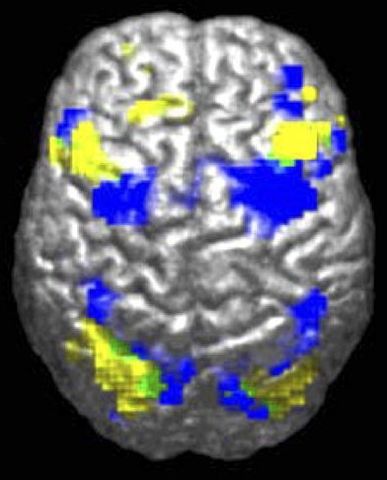

English: fMRI-derived image of difference between brains of autistic and control groups. Legend reads "Activation during visuomotor coordination: Autism Group [yellow], Control Group [Blue], Overlap (both groups) [green]". for Laurent Mottron*, "Even researchers who study autism can display a negative bias against people with the condition. For instance, researchers performing functional magnetic resonance imaging (fMRI) scans systematically report changes in the activation of some brain regions as deficits in the autistic group — rather than evidence simply of their alternative, yet sometimes successful, brain organization".

Français : Imagerie IRMf montrant les différences d'activité du cortex cérébral lors d'une activité de coordination visualo-motrice chez des personnes autistes et appartenant à des groupes-témoin. Les zones activées apparaissent jaunes pour le groupe des autistes [bleu pour le groupe de contrôle et vert quand elle est la même pour les deux groupes. Pour Laurent Mottron, neuropsychiatre et spécialiste de l'Autisme, les différences d'activation de certaines régions du cerveau montrées par l' imagerie par résonance magnétique fonctionnelle (IRMf) pourraient ne pas être seulement à considérer comme une preuve d'un trouble du fonctionnement du cerveau, mais aussi la preuve d'une organisation alternative du cerveau (observée comme efficace, par exemple lors de tests d' intelligence non-verbale).(Source : Laurent Mottron, Changing perceptions: The power of autism ; Nature 479, 33–35 (03 November 2011) ; doi:10.1038/479033a En ligne : 2011-11-02)

Source Figure 1A of: Powell K (2004). " Opening a window to the autistic brain". PLoS Biol 2 (8): E267. DOI: 10.1371/journal.pbio.0020267. PMID 15314667. PMC: 509312.

Author Ralph-Axel Müller